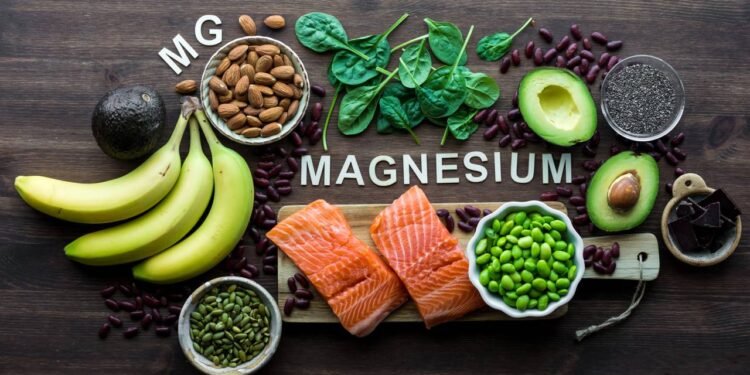

Existem várias formas de magnésio, e a escolha influencia a absorção e o objetivo do uso. O magnésio glicinato costuma ser associado ao relaxamento e ao sono, enquanto o magnésio citrato é mais usado quando também se busca melhora do trânsito intestinal.